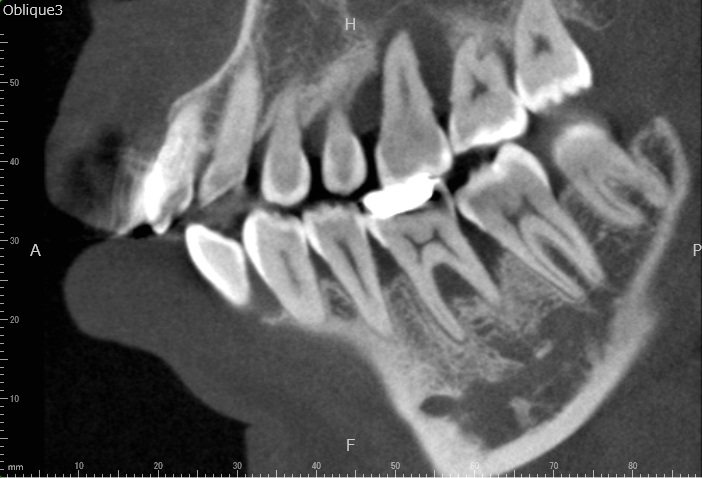

Case2

術前

術中

術後

| 治療名 | 再生療法 |

|---|---|

| 治療説明 | 右下6に重度の歯周病があり、通常の歯周治療でも改善しませんでした。歯周組織再生療法を行い、吸収してしまった骨を再生し、今後の歯周病の進行リスクを減らす事ができました。歯肉退縮もあったため同時に結合組織を移植し、骨と歯肉の再生を同時に行っています。 |

| 治療回数・期間 | 6ヶ月 |

| 副作用とリスク | 手術後に出血、腫脹、疼痛が生じることがあります。手術後は術部の創傷安定のためにブラッシング制限、食事制限があります。手術が複数回となることがあります。 |

| 料金(税込) | 再生療法:165,000円 結合組織移植:55,000円 総額:220,000円 |